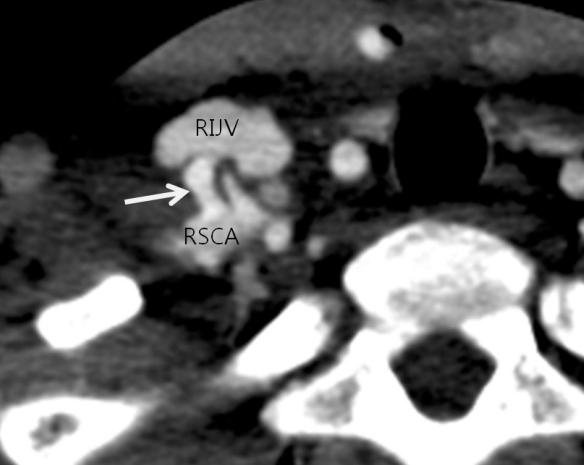

Fig. 2

Right subclavian arteriogram shows the arteriovenous fistula (white arrow). The fistula was seen as an ovoid spot because of posteroan terior direction.